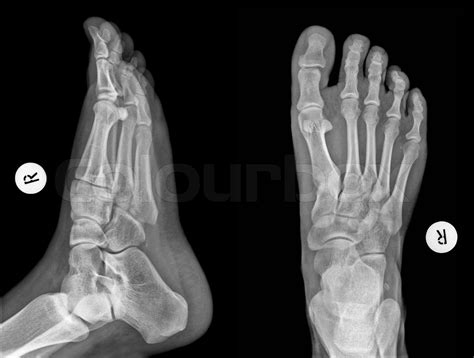

A Normal Foot Xray typically includes several standard views to provide a comprehensive assessment. These views include:

View Description

Anteroposterior (AP) View Shows the front of the foot, including the toes, metatarsals, and tarsal bones.

Lateral View Shows the side of the foot, providing a profile view of the bones and joints.

Oblique View Shows the foot at an angle, offering a different perspective on the bones and joints.

Axial View Shows the foot from above, focusing on the metatarsals and phalanges.